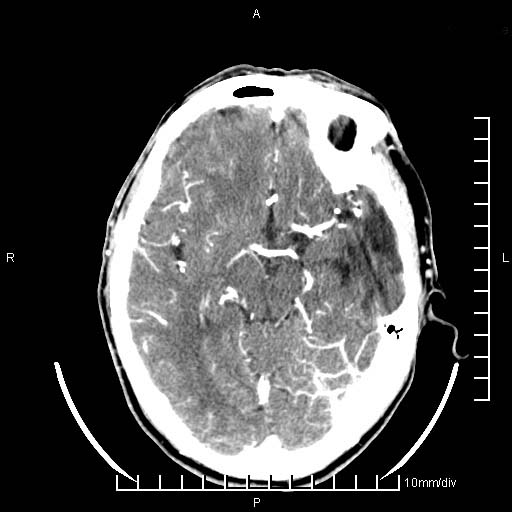

临床以双下肢浮肿,疼痛收治,无明显神经系统症状,既往无梗塞,出血病史。左颞叶见低密度灶,考虑什么?

考虑左侧颞叶脑软化灶。

无强化 无占位 软化灶吧

无强化、 无占位、局部脑沟增宽, 软化灶吧。